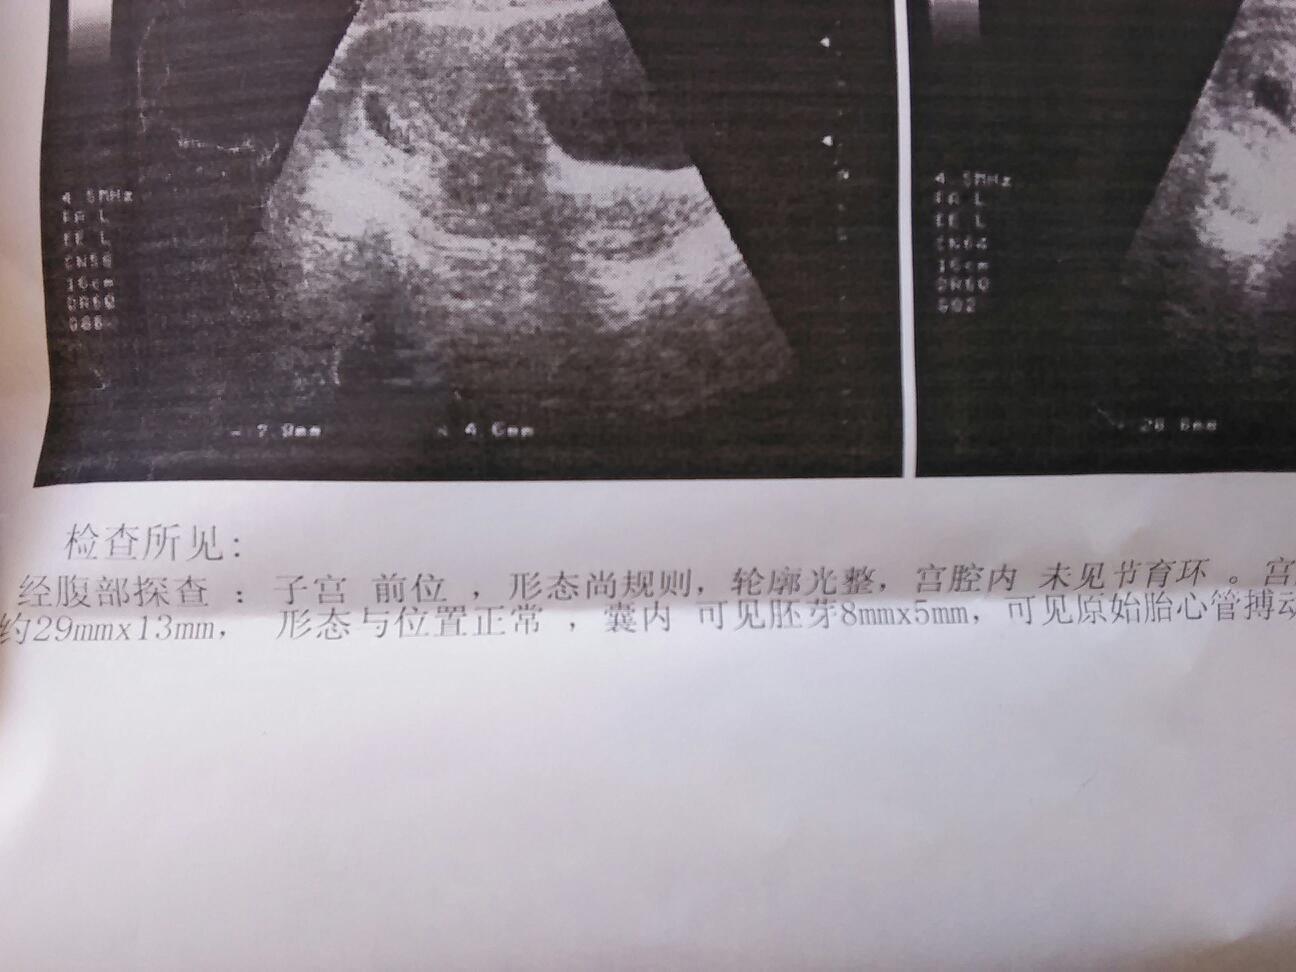

每次去检查都是我一糟菜个人去。坐公交车来来回回。颠死我了。医生还说我要保胎。打印趋香针。宰敲

胎心都有了……